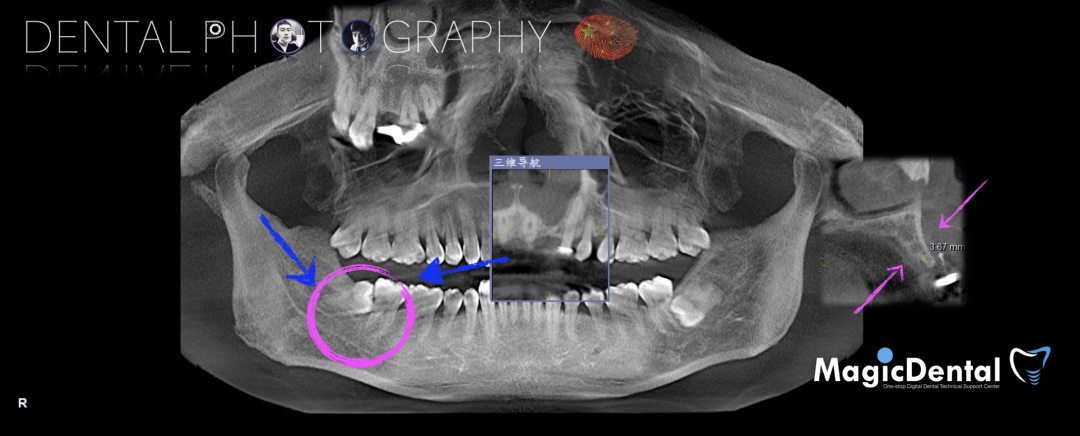

术前CBCT

22缺失,且牙槽骨唇颚侧宽度较窄,38,48近中阻生。

治疗计划:水平骨增量,拔除四区近中阻生智齿,下颌升支外斜线处取块状骨,移植骨块至受区(22唇侧),种植修复22缺失牙。

制作种植导板,局麻下切开,翻瓣彻底暴露术区,取出骨钉。

术后3个月CBCT及X线片。